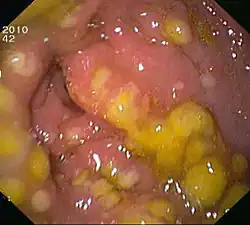

À la coloscopie, on peut constater la présence d'une membrane tapissant les parois de l'intestin, d'où le nom de la maladie.